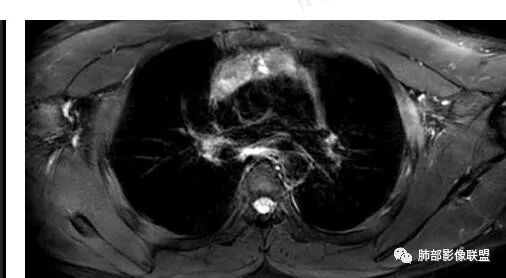

16岁男性,体检发现纵隔病变,提示无症状

前纵隔胸腺区病变

按分叶一边一个

大家看看这病灶信号

看看这个内部结构

是分叶还是两个病灶?

两个

两部分

多个病灶

问题是不是都是结节状,部分是条带状

胸腺内的

多发病灶

从MR看结构松散

不太符合肿瘤

首先考虑非肿瘤性病变